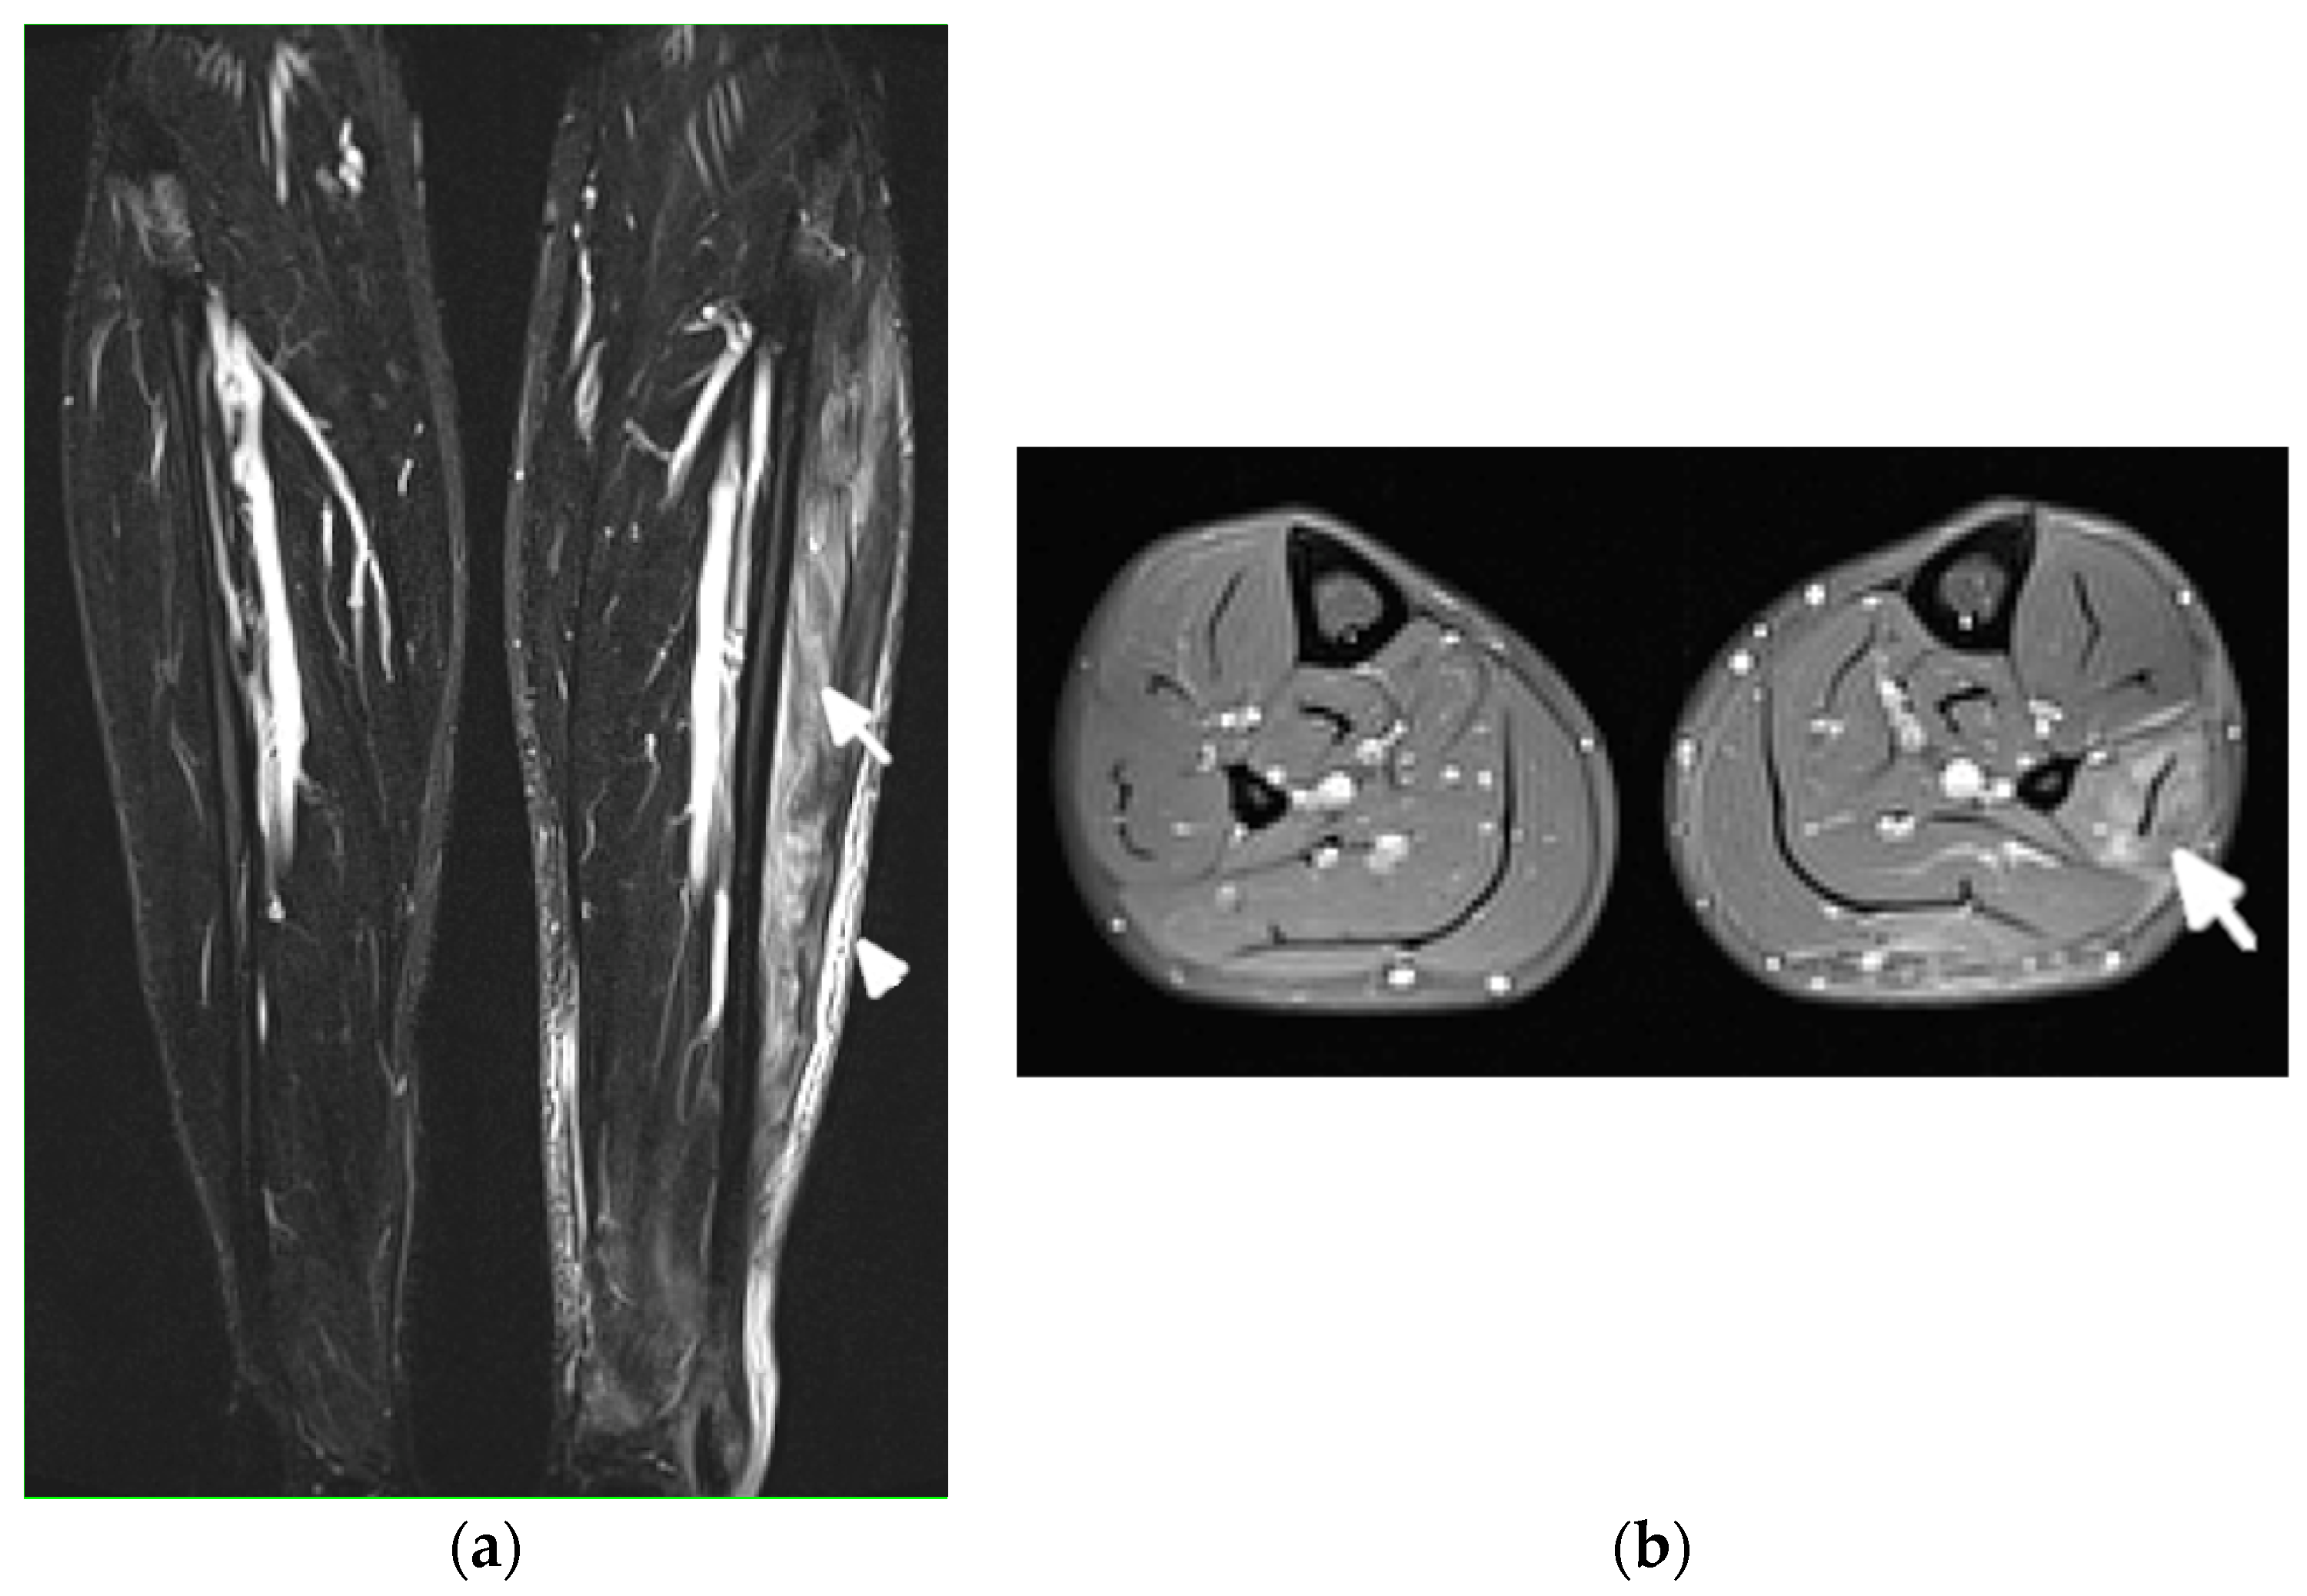

MRI is the most appropriate modality for the evaluation of muscle involvement, despite its low specificity, and US plays a complementary role [1,19] (Figure 9). MRI is used in the differential diagnosis and as a follow-up to a therapeutic response, and is useful to define the biopsy site [1,19]. Fat-saturated, fluid-sensitive MR sequences with long time until echo recovery are the most sensitive for identifying acute inflammation, manifesting as areas of high signals within the muscle [19]. Inflamed muscles also demonstrate contrast enhancement (Figure 9). In the chronic phase, involved muscles may undergo fatty infiltration with or without a loss of muscle bulk. These are seen on MRIs on T1-weighted sequences as areas of high signal intensity, replacing the normal intermediate signal of muscle fibers [19].

Figure 9.

Magnetic resonance (MR) imaging of lower legs of a 34-year-old male with systemic lupus erythematosus with myositis. (a) Coronal T2 turbo inversion recovery magnitude and (b) axial postcontrast T1-weighted MR images with fat saturation show increased signals in the muscles of the lower left leg (arrows), especially peroneus brevis and the lateral head of gastrocnemius, and to a lesser extent, soleus musculature, with heterogeneous enhancement in (b) after the administration of a gadolinium base contrast agent. In (a), note the subcutaneous edema around the left lower leg (arrowhead).

Diagnosis of ON and fractures is based on MRI in early stages (Figure 12) and radiography in advanced stages, like in adults.

Figure 12.

Magnetic resonance (MR) imaging of the femoral head osteonecrosis (ON) in a 14-year-old female with juvenile systemic lupus erythematosus. (a) Coronal and (b) axial proton density-weighted with fat saturation (right) MR images of the pelvis and right hip show a geographic serpiginous lesion in the right femoral head, with a bone marrow edema irregular contour and demarcation line consistent with ON (arrow).